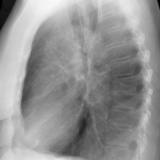

RLL Collapse  1 Lateral

Date: 02/28/2004

Views: 3187